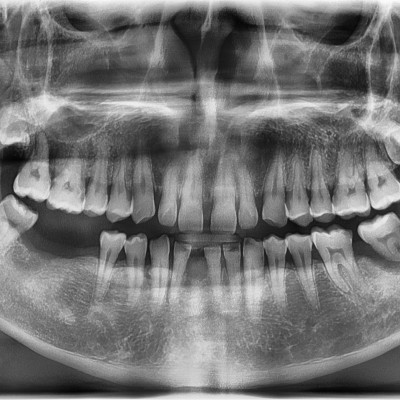

#18,48 사랑니 발치 #18,48 사랑니 발치 구강 외과 전문의가 당일 발치했습니다. ------------------------..

#48 사랑니 발치 (#47 포함) #48 사랑니 발치 (#47 포함) 구강 외과 전문의가 당일 발치했습니다. --------------------..

#28,38 사랑니 발치 #28,38 사랑니 발치 구강 외과 전문의가 당일 발치했습니다. --------------------------..

#28 사랑니 발치(#27포함) #28 사랑니 발치(#27 포함) 구강 외과 전문의가 당일 발치했습니다. ---------------------..

#38 사랑니 발치 #38 사랑니 발치 구강 외과 전문의가 당일 발치했습니다. -----------------------------..

#48사랑니 발치 #48 사랑니 발치 구강 외과 전문의가 당일 발치했습니다. -----------------------------..

#48 사랑니 발치 #48 사랑니 발치 구강 외과 전문의가 당일 발치했습니다. -----------------------------..